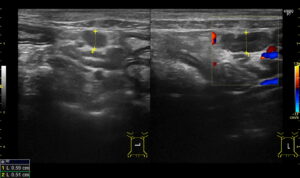

- 画像検査

レントゲンやエコー検査を実施

消化管の肥厚や消化管リンパ節の腫大を認めることが多い

エコーにてリンパ節の腫大を認める